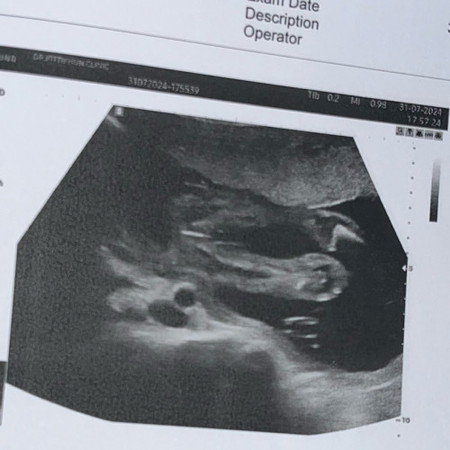

อัตราซาวด์คุณหมอบอกว่าน้องเป็นผู้หญิง แม่ๆคนไหนได้น้องผู้หญิงบ้าง แบบนี้ชัดเจนไหมม จะเปลี่ยนแปลงไหม 22 วีคค่ะ👶🏻

หมอบอกก็น่าจะ 90% แล้วนะคะ